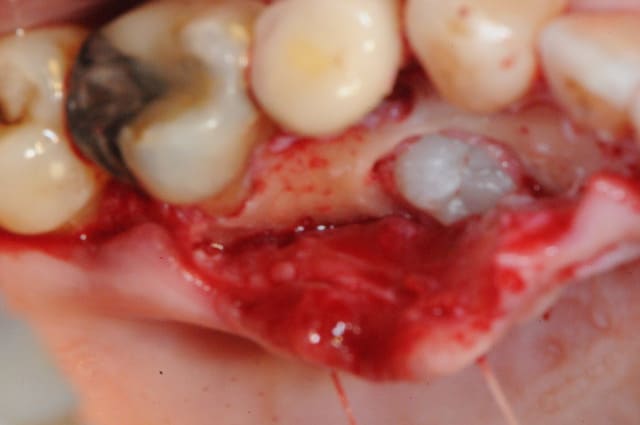

bon , fin du suspense.

1 aspect extérieure

2-3-4-5 décollement

6 l’objet du délit...